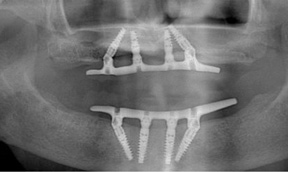

Severe maxillary atrophy may have a different etiology compared to that of the mandible, but the resultant resorption is no less debilitating. Grafting in the upper arch is increasingly less common with the advent of implant types such as zygoma that are anchored in remote bone and offer a far less traumatic and functionally improved option, especially for an aging patient. This is illustrated in Figure 4 and Figure 5. The patient had worn both a removable partial denture and full lower denture for more than 40 years with resulting severe maxillary atrophy opposing a natural dentition. Four zygoma implants were placed using the "quad" approach9,10 in lieu of a bone graft procedure (Figure 4). The final restoration remains in function in the patient's seventh decade (Figure 5).

Fig 4. Four zygoma implants placed using “quad” approach.

Figure 4

Fig 5. Final restoration remains in function.

Figure 5